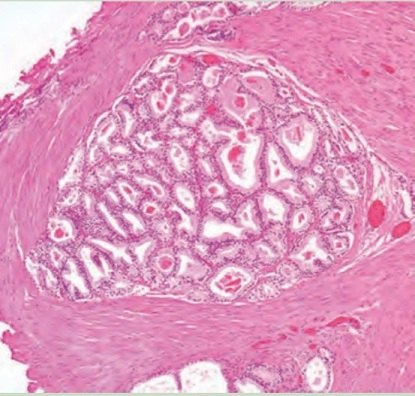

1、前列腺癌的Gleason评分,这个分数相当于对前列腺癌的“人品”打了个分。分数高低对预后有影响,对肿瘤复发后的治疗选择有指导;